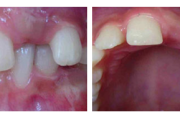

Ravijärgne seis. Jäävhammas on täielikult lõikunud.

Puudub ülemine tsentraalne intsisiiv, kuid külgmised lõikehambad on juba lõikunud.

Puudub ülemine tsentraalne intsisiiv